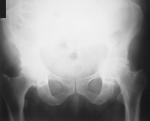

骨盆-双侧髋部前后位X线片(图1)和左侧髋部X片(图2),结果显示髋臼前突。临时诊断为强直性脊柱炎急性发作。

图1: